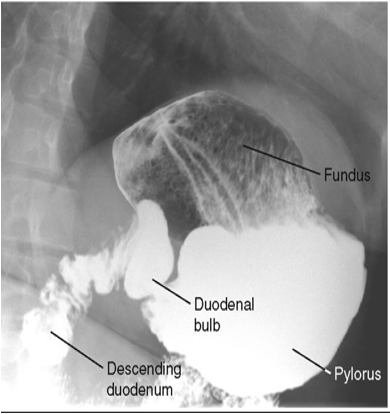

What position is this patient in?

Lateral (Spine is lateral and you see the retrogastric space)